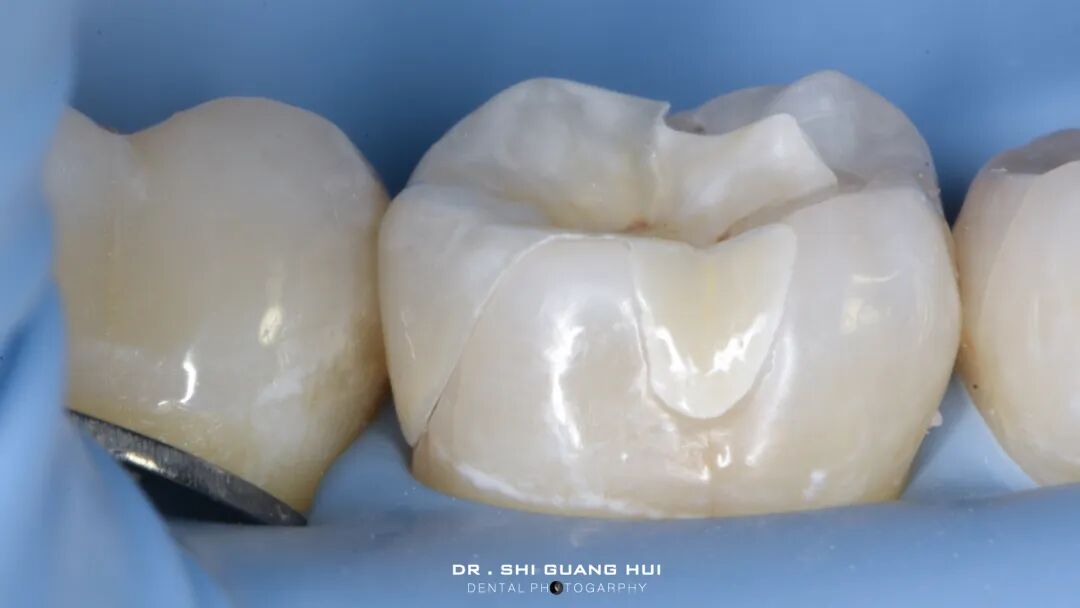

橡皮障隔离患牙,去净腐质,然后进行详细的生物力学分析,远中舌尖无牙本质支撑,需要牙尖覆盖,降低1.5mm左右,远中颊尖厚度足够。近中邻面边缘嵴完整,远中邻面边缘需要进行CMR。

圈型成型片完美隔离,喷砂牙本质表面,将牙本质表面进行37%磷酸酸蚀15秒,轻轻风干5秒后涂布粘接系统,进行IDS。

进行IDS,远中邻面进行CMR

进行牙体预备,抛光牙面,保持内线角圆钝,检查功能尖和洞缘的距离。

修复体制作完成,检查边缘密合性,邻面接触。